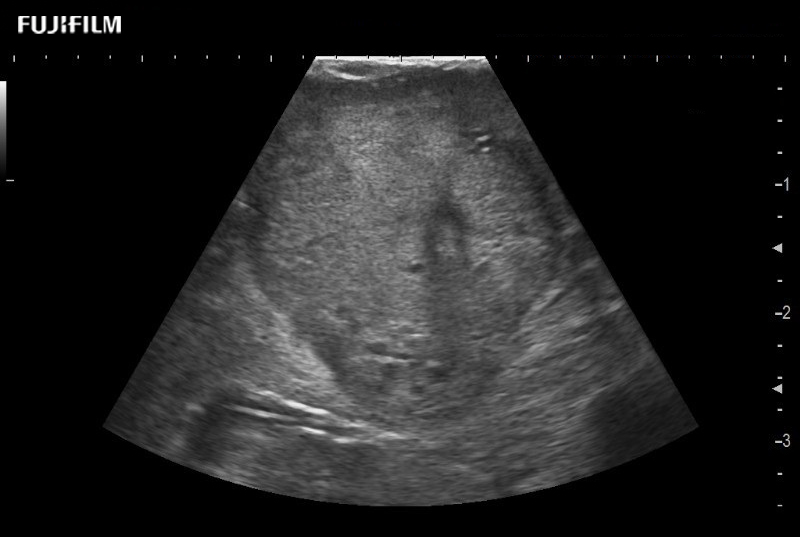

for use during robotic, laparoscopic and open surgical procedures: Tumor localization & staging, Ablation, Resection, Biopsy, Transplant, Abdominal exploration, Microsurgery

Our dedication to Robotic Surgery allows us to offer superior image quality, outstanding system reliability and intuitive use of cutting edge technology.

Curved array deep penetration “T” style finger-grip transducer for open surgical procedures.